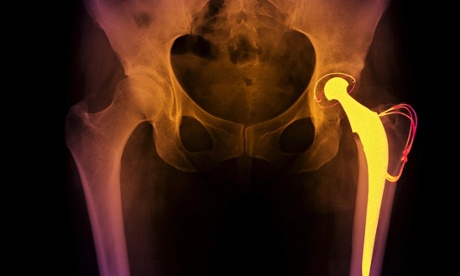

Hip operations are costing some parts of the NHS more than double the amount they should, the report revealed. Photograph: Voisin / Phanie/Rex Features

Hip operations are costing some parts of the NHS more than double what they should, the report revealed. Often the hips used do not last as long as less expensive versions, meaning patients need more replacements and follow-up care, costing the NHS up to £17m extra every year.